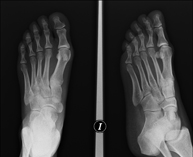

- RX Extremidades

Técnica mediante la cual, utilizando rayos X, se obtienen imágenes del interior de las extremidades para su estudio, especialmente de los huesos. Indicaciones: traumatismo, infecciones articulares.